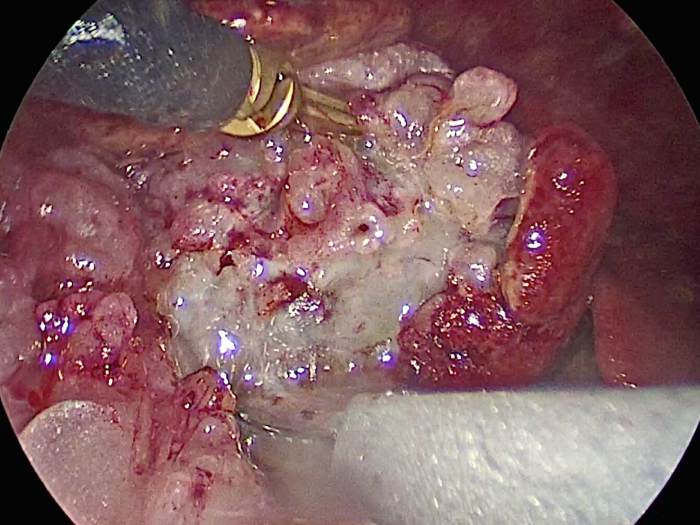

犬4kg。犬の腹腔鏡下胆嚢摘出術。症例は非常に癒着がひどく胆嚢を剥離するのが大変だった。 4ポートでの摘出となったが出血は少なく摘出が可能であった。 CLARA&CROMAという新しいモードで手術している。 これは暗いところ明るくし、CROMAは赤を強くしコントラストをつけることにより血管一本までしっかりと確認することができる。 少しギラギラするが、手術しやすくなる。

胆嚢の周囲の脂肪や膵臓、十二指腸が激しく癒着し剥離が困難な状態でした。 胆嚢は全く確認することができませんでした。

少しずつ癒着を剥がして胆嚢が確認できるようになってきました。

こんなに癒着していることはあまりないので過去に膵炎や胆嚢炎を起こし苦しい時期があったことが推測されました。

それにしてもなかなか胆嚢はでてきませんでした。

摘出した胆嚢はカチカチで中にはゼリー状の硬い物質が詰まっていました。

手術は丁寧に剥離していったため時間がかかってしまいました。

症状がなかったので、こんなに大変な状態になっているとは。